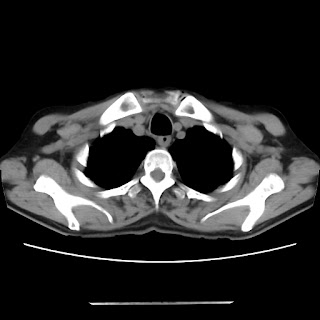

A 54 years old man with intermittent cough with expectoration and shortness of breath since childhood (Radiology)

Radiological images: